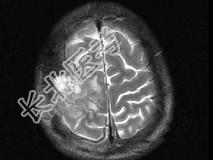

单项选择题男,63岁, 反复抽搐30余年加重伴左侧肢体活动不利活1月余,PE: 右顶部约4cm×5cm大小隆起包块质硬,不能活动, 右上下肢肌力Ⅴ,左上下肢肌力Ⅳ+, 根据所提供图像,最可能的诊断为 ( )

A、右顶骨(副脊索瘤)或称为肌上皮瘤

B、右顶骨转移瘤

C、右顶骨骨瘤

D、右顶骨血管瘤

E、右顶骨胆脂瘤